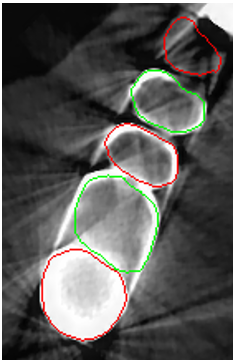

Despite all the appealing features from the contour propagating scheme, level-set methods demonstrate a common limitation, i.e., it is difficult to delineate unclear boundaries (Fig. 2). In a CBCT, the boundaries between the tooth root and the alveolar bone have weak edge characteristics (i.e., a low magnitude of gradient; Fig. 2a) and the presence of severe metal artifacts (Fig. 2b), which hinder the accurate propagation of a contour-based level-set method. Furthermore, level-set methods require tedious manual user interaction to define the initial contour [4, 5, 7], indicating a semiautomated algorithm.

The manual seeded level-set methods [6, 7] demonstrate inferior performances while segmenting teeth with predominant metal artifacts (Table II). The energy-based (i.e., level-set function) algorithmic approach failed while defining an optimum stopping criterion (Fig. 12b). The AJI measures for level-set methods are omitted because the box detectors do not exist in the level-set-based methods. In particular, the low precision and sensitivity values indicate that level-set methods have over-segmented or under-segmented the teeth in many cases (Figs. 12b and 13a). The accuracies of the Mask-RCNN [17] and ToothNet [11] showed comparable performance to the level-set-based methods. The instance segmentation framework successfully detected and segmented the teeth automatically. However, it failed to detect all the teeth regions accurately, which resulted in a degradation of the segmentation performance. Moreover, the performance of the segmentation itself also showed low accuracy owing to the metal artifacts (Figs. 12c and 12d). Figure 13 illustrates the more severe conditions of metal artifacts. The performance of the detection and segmentation processes significantly degraded in ToothNet [11] (Fig. 13b) and Mask-RCNN [17] (Fig. 13c). Conversely, our proposed method outperformed the other state-of-the-art methods (Figs. 12e and 13d); further, the comparison between the PA- and non-PA-based results also demonstrated that the employment of a PA detector significantly improved the proposed architecture (Table II). The superior AJI value clearly shows that successful detection improved the overall performance.